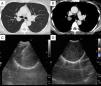

Presentación del casoUna mujer de 47años fue remitida a nuestro hospital para un estudio diagnóstico de un tumor pulmonar. Se le practicó una lobectomía derecha del tiroides a causa de un adenocarcinoma papilar de tiroides a los 45años de edad. La paciente estaba afebril y las constantes vitales eran normales. No había ganglios linfáticos palpables y la auscultación pulmonar fue normal. Los análisis de bioquímica y hematología fueron normales. La radiografía de tórax mostró un nódulo de 2cm en el campo pulmonar superior derecho. La TC de tórax (fig. 1A,B) reveló la presencia de un nódulo redondeado, bien definido, de 2,4cm en S2, adyacente al bronquio del lóbulo superior derecho. La broncoscopia mostró una lesión submucosa y el bronquio del lóbulo superior derecho estaba casi ocluido. La EBUS mostró un tumor hipoecogénico, bien definido, con una cápsula ecogénica y un refuerzo acústico posterior (fig. 1C,D). No se detectó una continuidad con el nervio. Se realizó una EBUS-TBNA, ya que podría haber resultado imposible obtener un diagnóstico histológico con una biopsia transbronquial. La muestra obtenida mediante EBUS-TBNA mostró áreas hipercelulares con proliferación de células fusiformes y área hipocelulares (fig. 2A,B). La inmunotinción para S-100 fue positiva (fig. 2C) y se confirmó un diagnóstico de schwannoma. No se utilizó una evaluación citológica rápida in situ. Se practicó a la paciente una tumorectomía porque existía la posibilidad de una neumonía obstructiva. El diagnóstico anatomopatológico de la pieza quirúrgica fue también de schwannoma.

En la ecografía, el schwannoma es un tumor hipoecogénico bien definido5. En algunos casos se detecta también una cápsula ecogénica, un refuerzo acústico posterior y una continuidad del nervio5. Pero estas características son las propias del schwannoma situado en las extremidades y en la superficie del cuerpo. Que nosotros sepamos, no se ha descrito la identificación de un schwannoma intrapulmonar con ecografía endobronquial. En nuestro caso, la ecografía endobronquial mostró una masa capsulada hipoecogénica bien definida, con un refuerzo acústico posterior, aunque no se detectó una continuidad del nervio. Estas características podrían ser útiles para diagnosticar un tumor de origen nervioso en el pulmón.